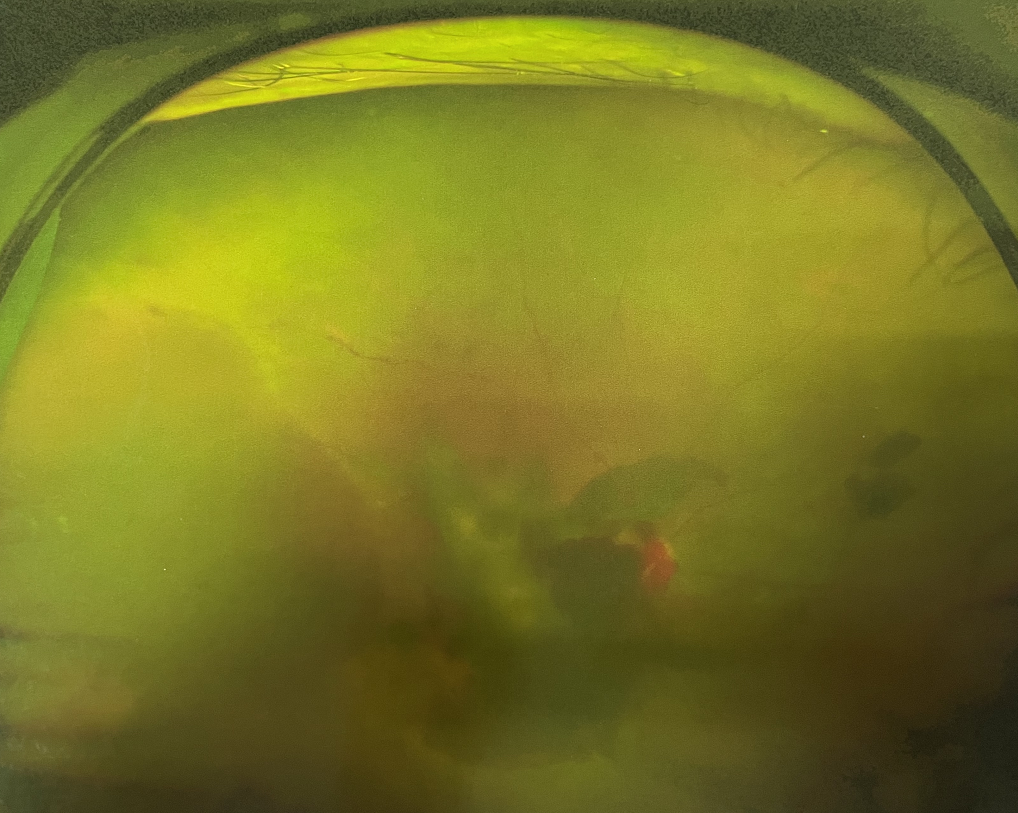

眼底出血不是獨(dú)立的眼病,而是由于眼球自己的病變和某些全身疾病的并發(fā)癥導(dǎo)致眼底的視網(wǎng)膜或脈絡(luò)膜出血,如果出血量大就會進(jìn)入到眼球的玻璃體內(nèi),從而影響視力,如果沒有得到恰當(dāng)?shù)闹委熆蓭砀鼑?yán)重的并發(fā)癥造成失明。

眼底出血的患者,如果出血量少,而且在視網(wǎng)膜周邊部可能沒有明顯癥狀,患者僅感到眼前有黑影浮動;如出血量多,將嚴(yán)重影響視力,甚至完全被黑影所遮擋僅剩光感;如出血位于視網(wǎng)膜的黃斑區(qū),患者視野中心區(qū)被暗影遮擋,周邊尚有部分視力。

先是散瞳檢查眼底,可以明確眼底出血的性質(zhì),出血部位和出血量有多少。眼B超檢查,對于眼底出血量特別多,無法看清眼底的患者,就需要進(jìn)行眼部B超檢查,以了解出血量,出血部位、有無合并視網(wǎng)膜脫離;還可以明確是否患有視網(wǎng)膜或脈絡(luò)膜的腫瘤。